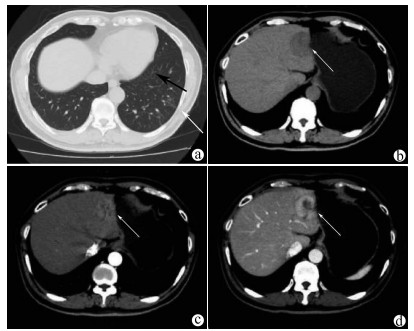

Complete remission after comprehensive treatment of lung metastases following liver cancer surgery: A case report